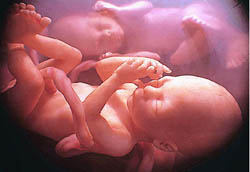

Bé 4 tuổi mang thai trong dạ dày

Các bác sĩ Trung Quốc đã vô cùng kinh ngạc khi phát hiện một bào thai không phát triển bên trong dạ dày của một cậu bé 4 tuổi, bị sưng phồng bụng từ khi mới sinh. Điều dị thường mãi tới gần đây mới được phát hiện khi cậu bé ở tỉnh Tứ Xuyên này gặp trục trặc về hô hấp. Tại bệnh viện, sau khi phát hiện dị vật trong dạ dày bệnh nhi, các bác sĩ đã phẫu thuật lấy bào thai ra

Giới truyền thông địa phương đưa tin, bào thai có kích thước chiều dài và chiều rộng khoảng 20cm. Nó đã có xương sống hình thành rõ ràng với 4 chi có các ngón tay và ngón chân. Bào thai cũng đã có ruột và toàn bộ cấu trúc của nó chiếm khoảng 2/3 diện tích dạ dày của bé trai nói trên. Theo các bác sĩ, đây là trường hợp mắc hội chứng Cryptodidymus hiếm gặp, trong đó cặp song sinh dính liền nhau trong quá trình mang thai của mẹ. Trong các ca cryptodidymus, một trong hai bào thai thường nhỏ, kém phát triển và ký sinh trong cơ thể anh/chị em song sinh của nó. Sau ca phẫu thuật loại bỏ bào thai ký sinh, cậu bé Trung Quốc hiện trong tình trạng sức khỏe ổn định.ngoài.